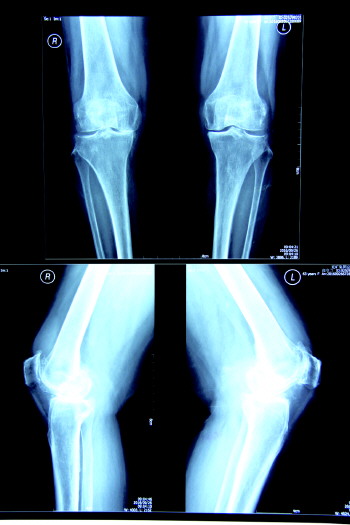

术前X光图

业务范围:骨外科设计的所有疾病,如各种骨及关节创伤及疾病、各种脊柱创伤及疾病,四肢创伤、断指(肢)再植、骨肿瘤等。尤其擅长骨关节内及近关节部位的骨折、脱位等复杂难治性骨折,骨性关节炎等退行性关节疾患的关节清理手术及各种人工关节置换手术,在骨折、关节镜、关节置换、股骨头坏死的早期治疗及显微外科方面处于本地区先进水平。

技术特色:科内拥有国内先进的移动式“C”形臂X光机,移动式骨科手术显微镜,美国“施乐辉”关节镜,大大提高了骨科手术成功率。临床和科研综合能力在本地区处于领先行列,如关节镜下肩袖损伤、肩胛盂唇损伤等关节疾患修复术、膝关节交叉韧带重建、关节镜下半月板全内缝合等。并率先在本地区开展了股骨头早期坏死髓芯减压钽棒植入术,已开展了肩袖损伤的开放手术及关节镜微创治疗取得了良好疗效。目前已完成全髋关节、膝关节置换及翻修术数百例,并开展了踝关节置换,取得了良好效果。